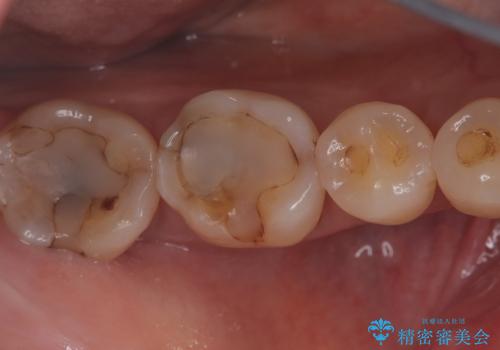

- 主訴:プラスチックの劣化が気になる。

咬合面にCR(コンポジットレジン)修復が広範囲にされており、劣化のしにくさや審美性からセラミックインレーでのやり替えとなりました。

今回残存歯質量から破折のリスクを説明し、クラウンでのやり替えも提案しましたが歯質切削量が多くなることから一度インレーで様子を見ることとなりました。